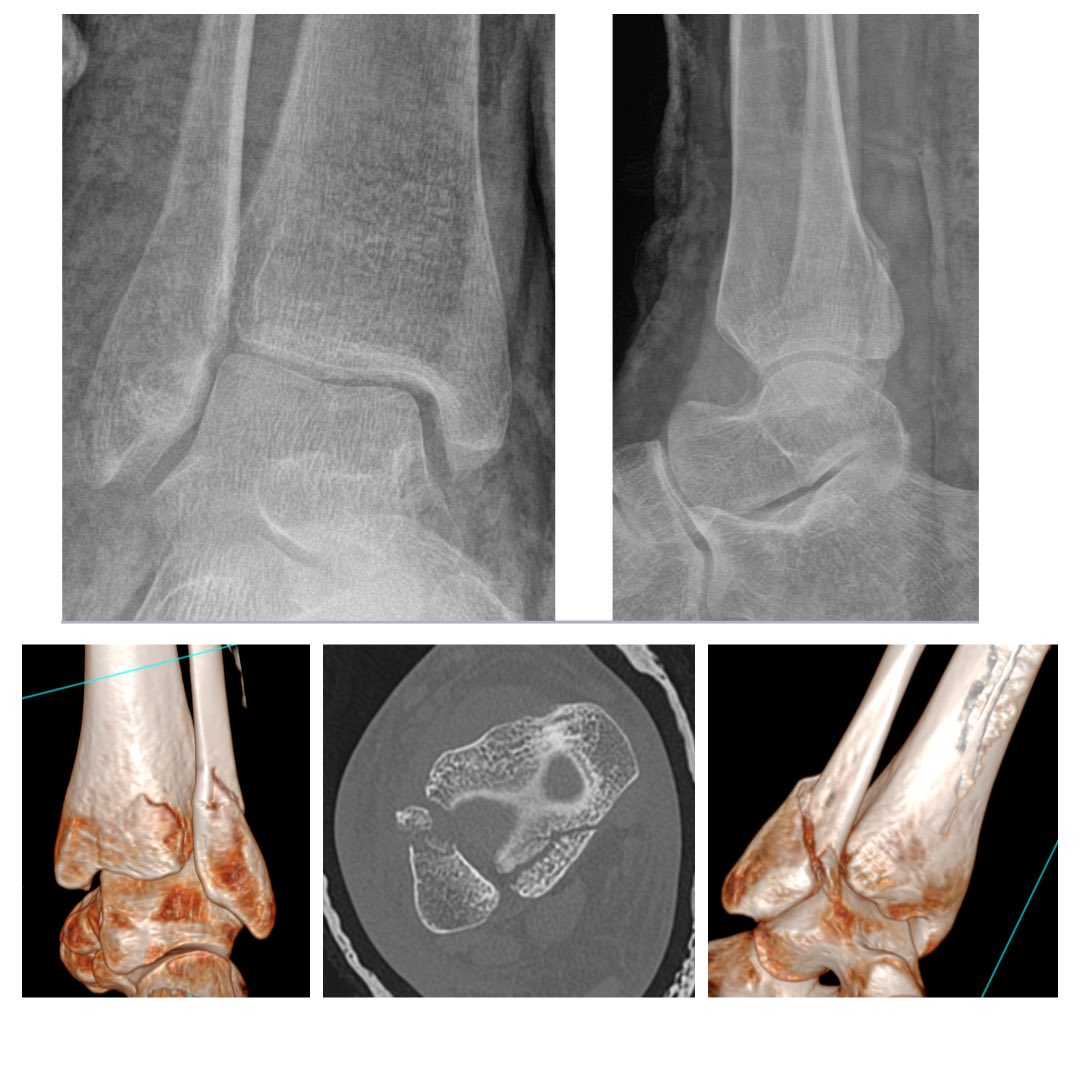

These just keep getting sillier stumble twist and fall giving me the craziest medial mal i recent history. tib post retiaculum avulsed chunks of the post colliculus. ant colliculus also comminuted. Type 2A post Mal / MPM Lyndon Mason #orthotwitter osteosynthesis.org/33209496-compl…